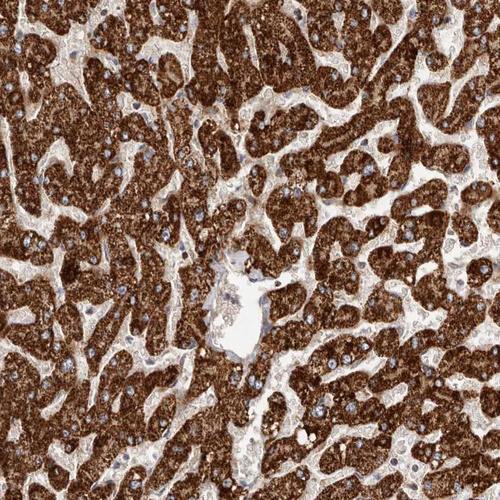

Immunohistochemical staining of human liver shows strong cytoplasmic positivity in hepatocytes.